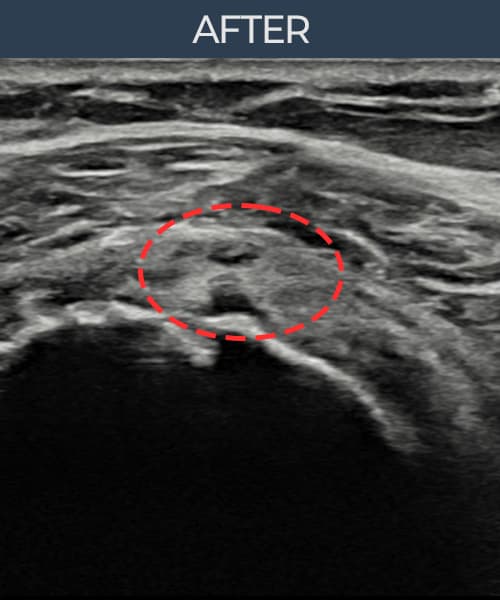

[経過期間: 23.07.31~23.09.27]

[縫縮術] 超音波検査にて左 棘上筋腱 부착부 광범위 部分断裂(13mm × 5mm (腱厚の約65%欠損))を確認。縫縮術施行後、腱の連続性が回復し、日常生活に復帰されました。